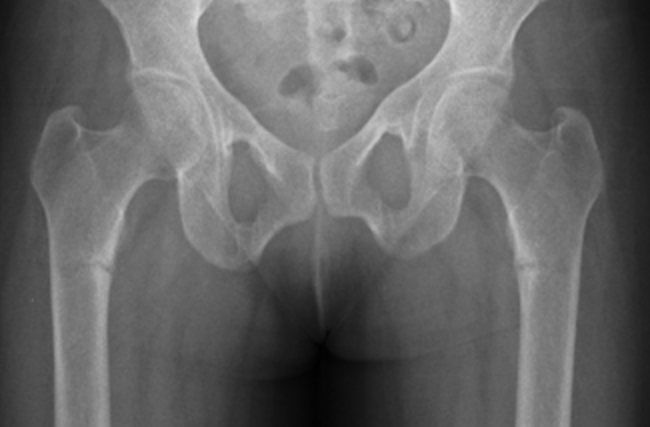

Xray

Periosteal stress reactions / beaking

Thickening of the lateral cortex

- tension side

- most common in the subtrochanteric region

- can be in shaft

Atypical femur fracture xrayAtypical femur fracture CTAtypical femur fracture CT 2

Lateral beaking subtrochanteric region

Lateral beaking femoral shaft